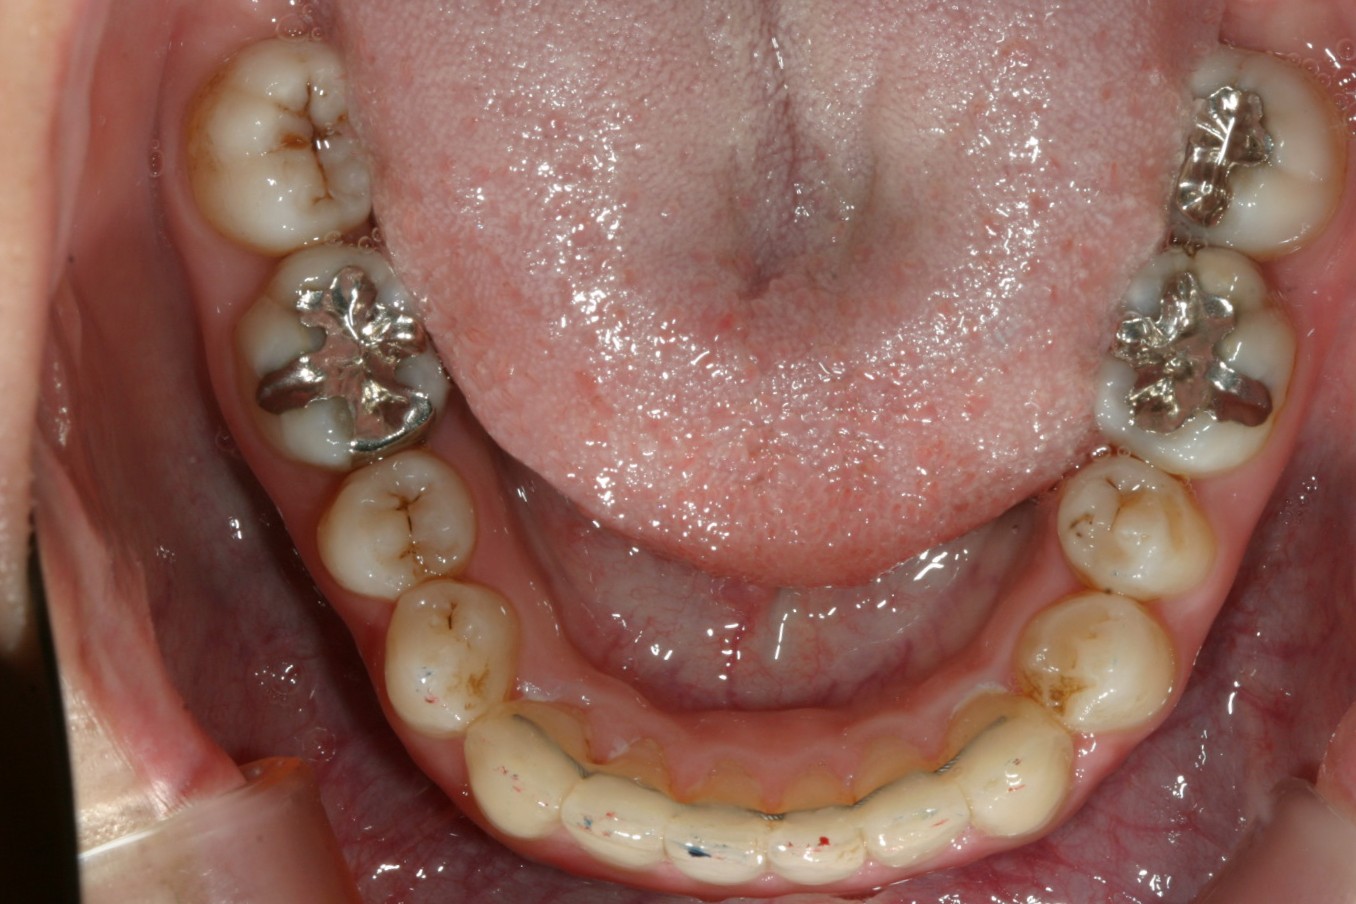

下顎の叢生も綺麗に取れています。